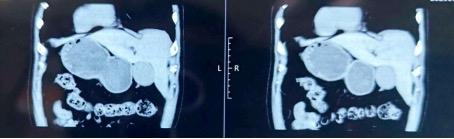

“镜面人”胸部、腹部CT及检查报告

来自山西的张大叔(化姓)便是一位“奇人”—他自幼便发现自己的心脏在右侧胸膛跳动。进一步的检查结果更令人惊讶:不仅心脏,他所有的脏器都发生了180°翻转!肝脏和胆囊移居左侧,胰腺和脾脏安居右侧,胃肠道的布局也与常人完全相反。

这种现象在医学上称为“内脏反位”,是一种罕见的先天发育变异,可分为部分内脏反位和全内脏反位。张大叔的情况属于后者,所有内脏都呈反向分布,就如同正常人在照镜子,因此也被形象地称为“镜面人”,发病率约为百万分之一。